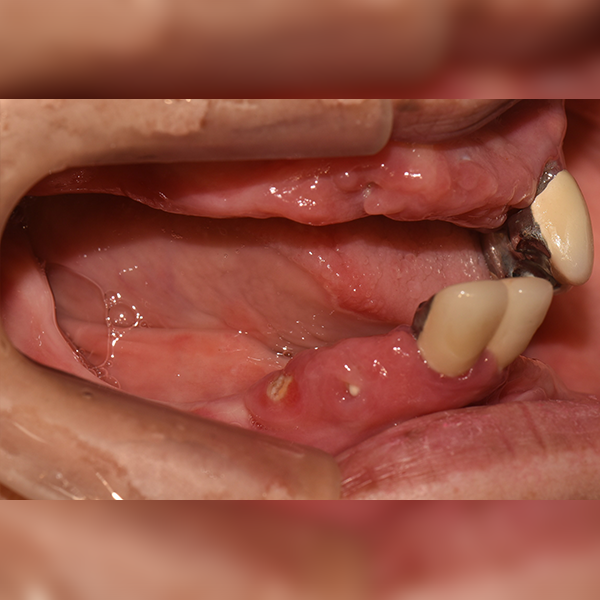

3. Тохиолдол.18 60-н настай Пак*Сүн 2019-12-09 / 2020-11-05

Oneday Шүдний эмнэлэг

Бүтэн эрүү / Яс шилжүүлэн суулгах | Унтуулгатай

Тохиолдол.18 60-н настай Пак*Сүн 2019-12-09 / 2020-11-05